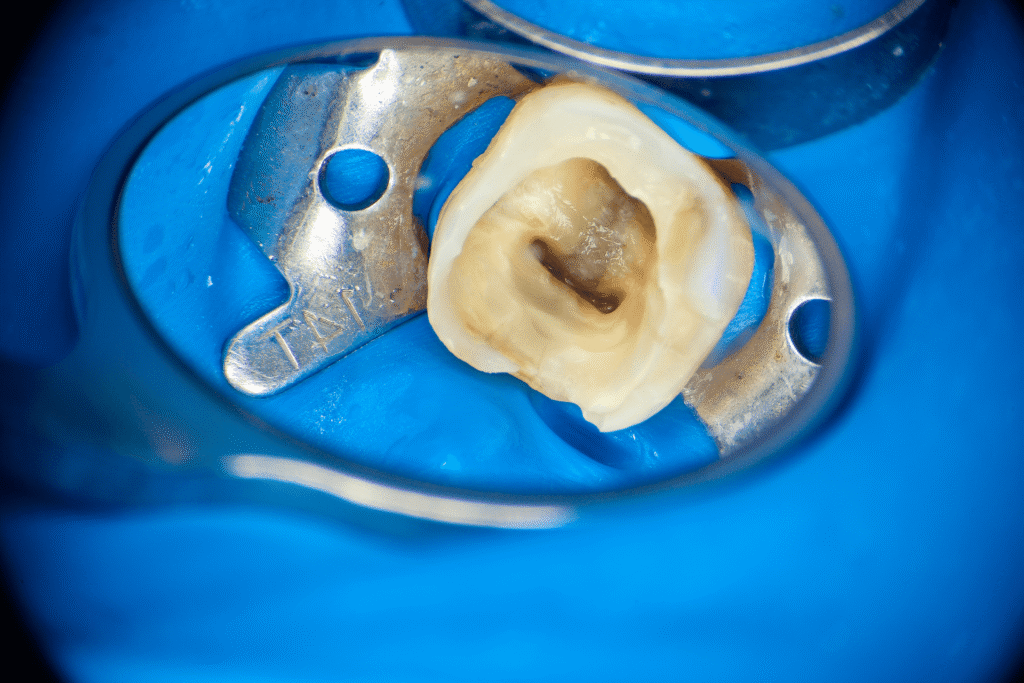

Pacjentka lat 54 trafiła do mojej kliniki skierowana z innego gabinetu celem leczenia endodontycznego zęba 46. W badaniu stwierdziłem znaczny zanik światła kanału korzeniowego. W badaniu tomograficznym stwierdziłem całkowity zanik kanału korzeniowego w strefie mezjalnej. Korzeń dystalny mimo widocznego światła kanału na CBCT, widoczne było wiele zwapnień w środkowej części kanału. Po wykonaniu dostępu endodontycznego zlokalizowałem materiał wypełniający kanał pozostawiony po poprzednim nieskutecznym leczeniu endodontycznym. Do usunięcia wykorzystałem laser 2780nm (25mJ/puls). W kolejnych etapach instrumentacji wspomaganie ultradźwiękami oczyściłem strefy mezjalną i dystalną. Instrumentacja themo-

mechaniczna polegała na zastosowaniu protokołu ciągłej chelacji wraz z użyciem lasera

2780nm z końcówką płaską (50mJ/puls) celem udrożnienia przestrzeni endodontycznych. Po wstępnym uzyskaniu drożności zastosowałem instrumentację maszynową wspomagająco celem udrożnienia przestrzeni. Finalnie obturacja z zastosowaniem ćwieków gutaperkowych kalibrowanych na WL i uszczelniacza na bazie krzemianów wapnia. W przeciwieństwie do tradycyjnych uszczelniaczy, nie wymaga mieszania, co eliminuje błędy w proporcjach i zapewnia powtarzalną konsystencję. Jest materiałem wysoce biokompatybilnym i bioaktywnym. Finalnie zamknięto ząb odbudową kompozytową tymczasową i skierowano na dalsze leczenie protetyczne do gabinetu kierującego pacjenta.